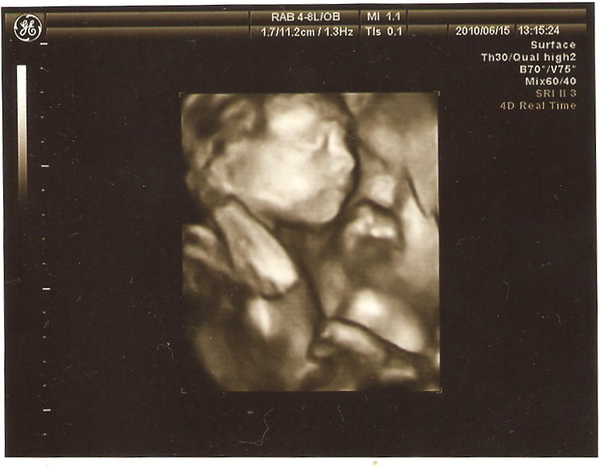

這張照片同事說:一副苦惱的樣子 XD

這張照片讓我們覺得:以後鼻子應該不會跟他老爸一樣扁...